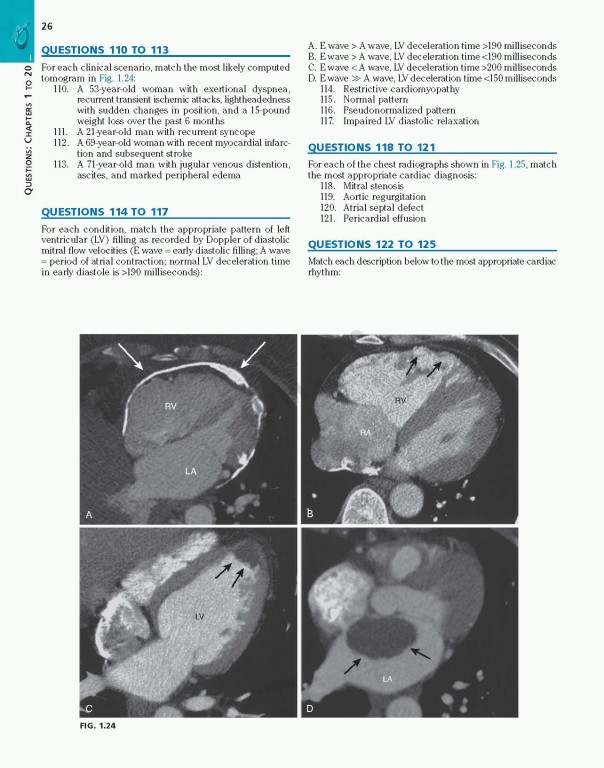

کتاب Braunwalds Heart Disease Review and Assessment 2019، بررسی و ارزیابی بیماری قلبی براونوالد ویراست یازدهم شامل تصاویر و تصاویر کاملاً رنگی که مطالعه شما را بهبود بخشیده و حفظ مواد پیچیده را بهبود می‌بخشد.

With more than 700 review questions derived from and keyed to the newly revised 11th Edition of Braunwald's Heart DiseaseBraunwald’s Heart Disease Review and Assessment, 11th Edition, is the perfect review tool for fellows, residents, and practitioners to prepare for board exams in cardiovascular medicine. Noted Harvard educator Dr. Leonard S. Lilly, with assistance from faculty and fellows at Brigham & Women’s Hospital, provides a thorough, clear, and concise overview of the entire field, helping ensure your mastery of all key aspects of today’s cardiology. This title is a one-stop resource for complete, authoritative coverage of the most important concepts in cardiovascular medicine – ideal for self-assessment, individualized study, and clinical practice.

• Contains full-color images and illustrations throughout, and numerous case studies that enhance your study and improve retention of complex material.